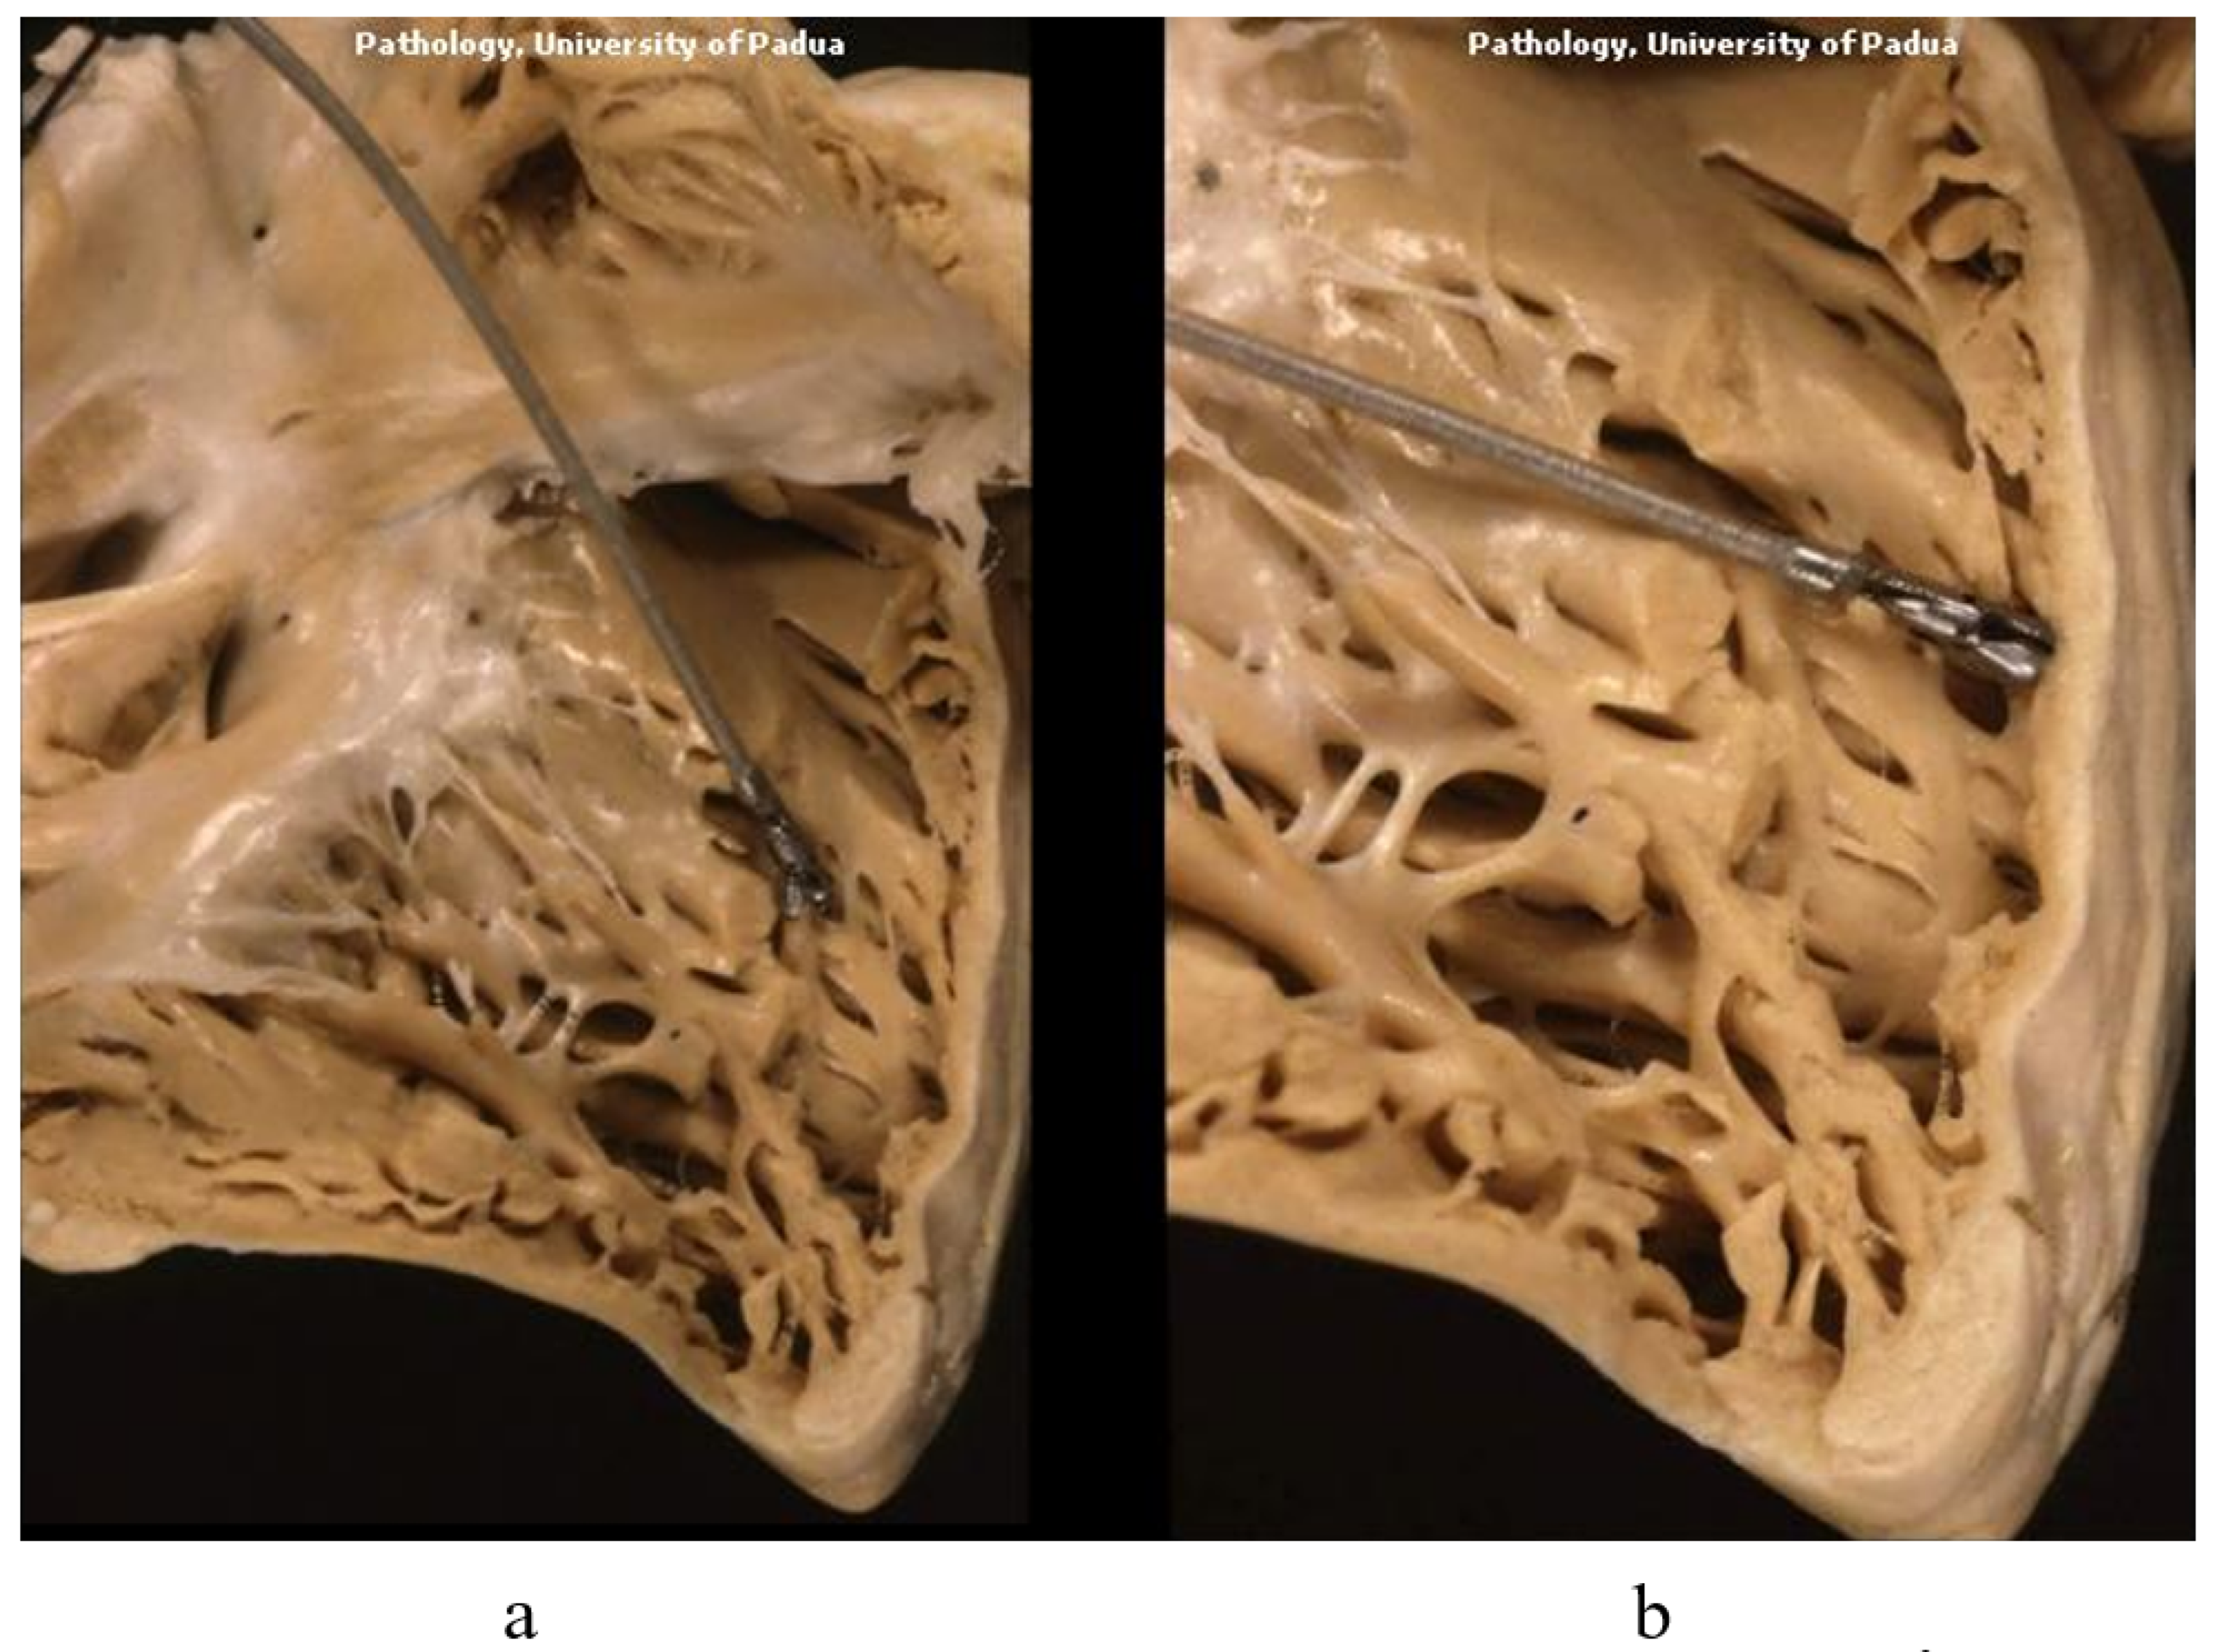

3. Arrhythmogenic Cardiomyopathy

7. Clinical Indications of Endomyocardial Biopsy